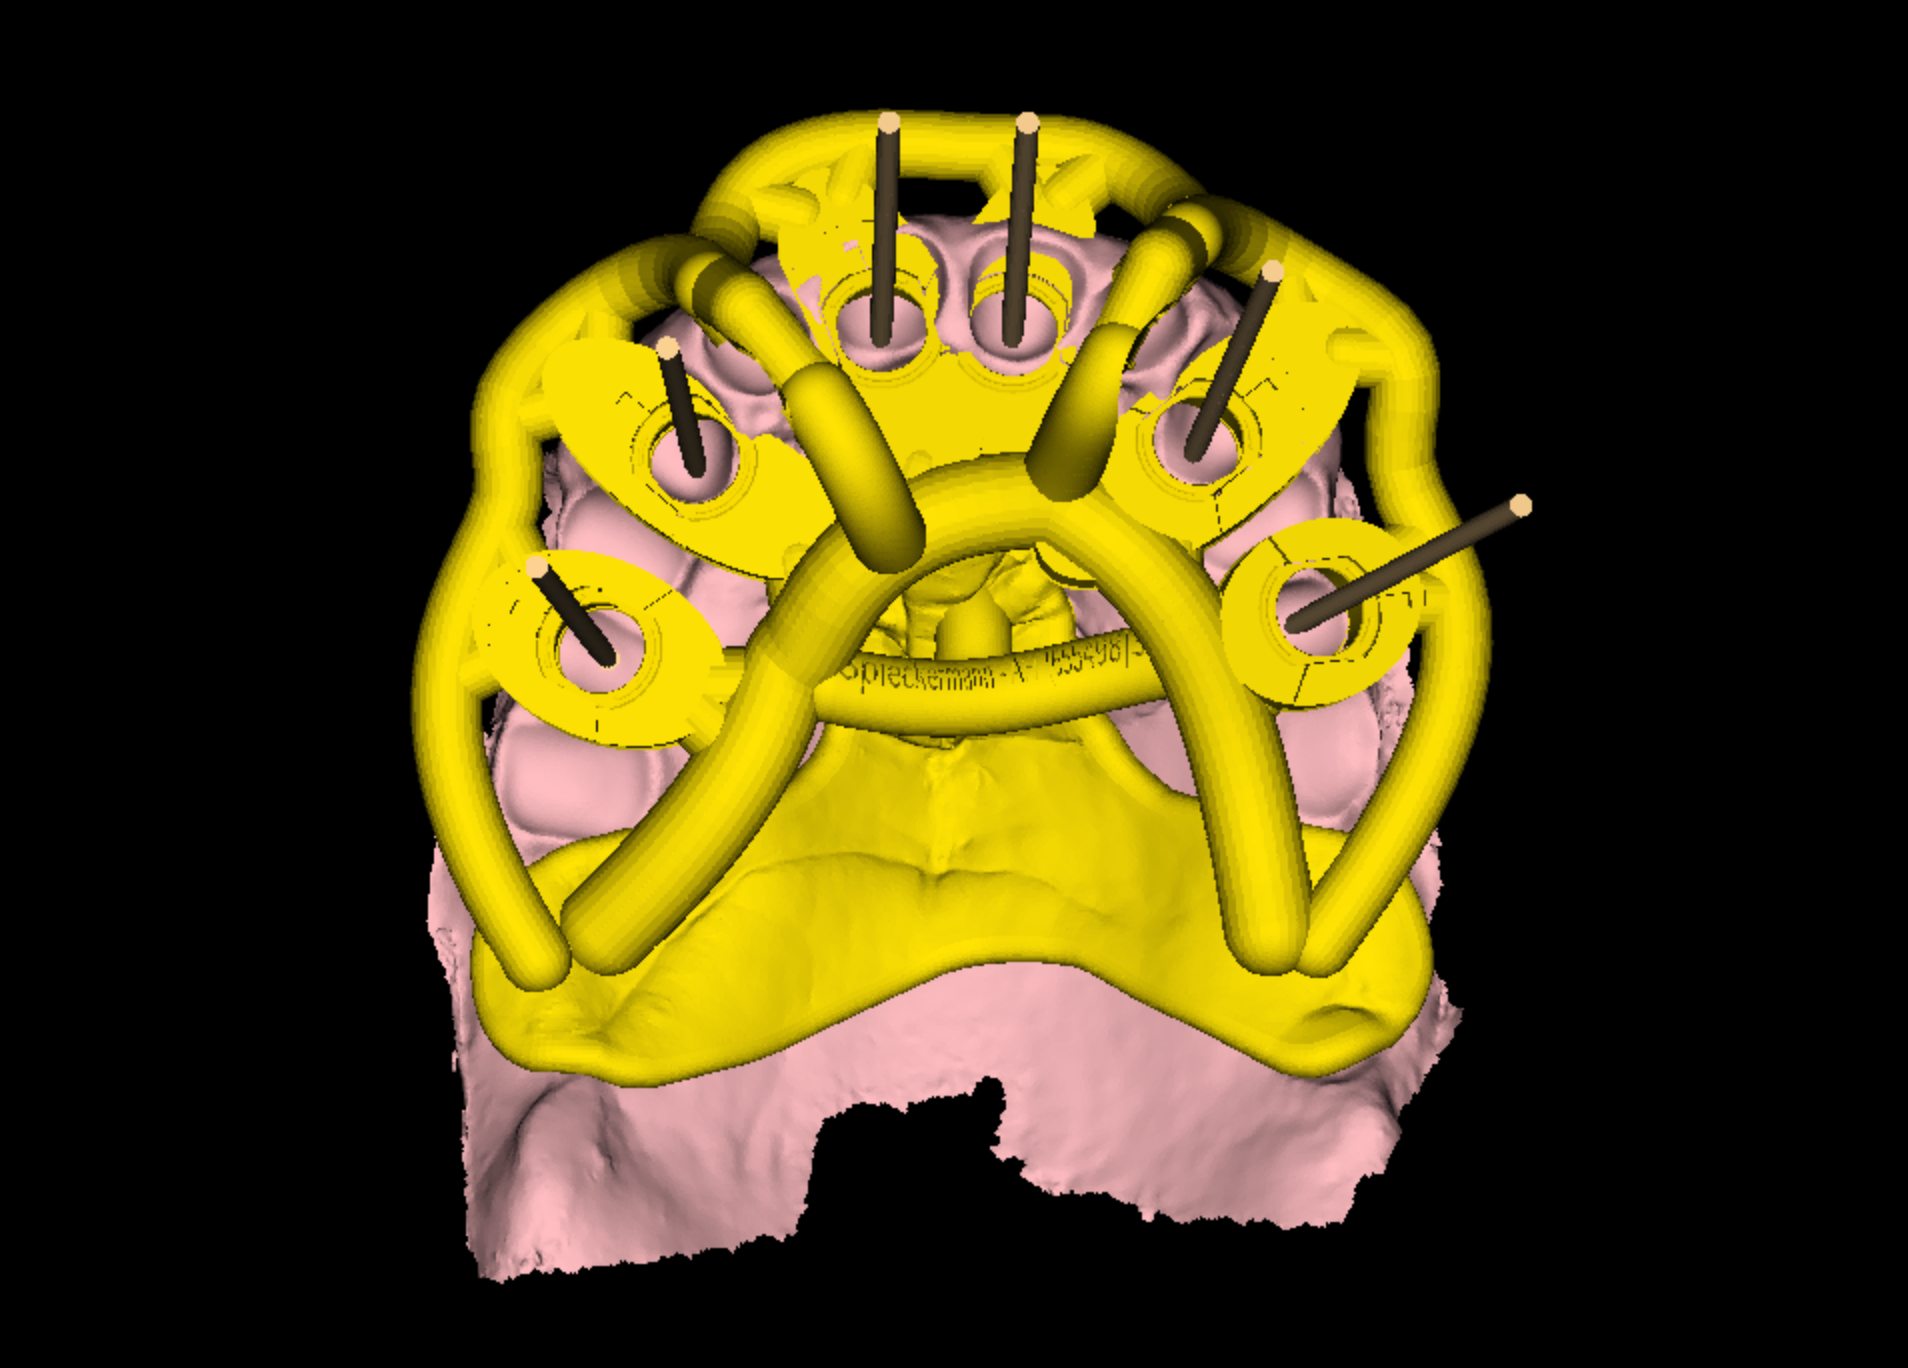

Initial diagnostics included CBCT imaging and full-arch intraoral scanning. A digital wax-up with an increased vertical dimension of approximately 2 mm was created to simulate functional and aesthetic improvements. Fully digital implant planning was carried out, and a SMOP tooth supported guide was designed, anchored in the region of the lateral incisors.

Following the extraction of teeth 13–23, the tooth-supported guide was positioned and stabilized, allowing precise, fully guided implant surgery. Multi-Unit Abutments were inserted according to the digital plan. Immediately post-surgery, intraoral photogrammetry was performed to record the implant positions with high accuracy, eliminating the need for conventional impressions or splinting.